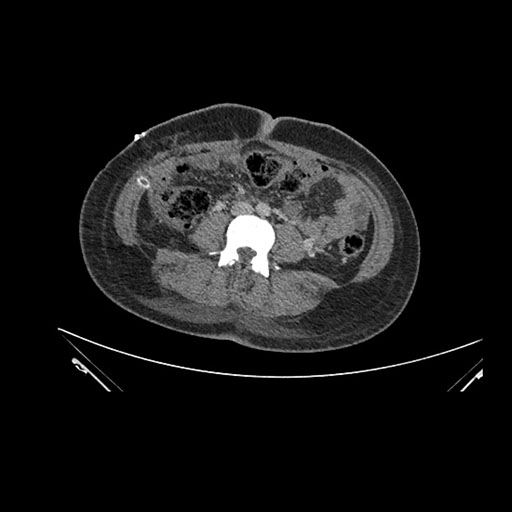

Imaging Analysis

Look through the patient's CT scan to identify any areas of concern for the necessary procedure.

Axial Venous

Based on initial findings, which issue(s) would you be most concerned about?